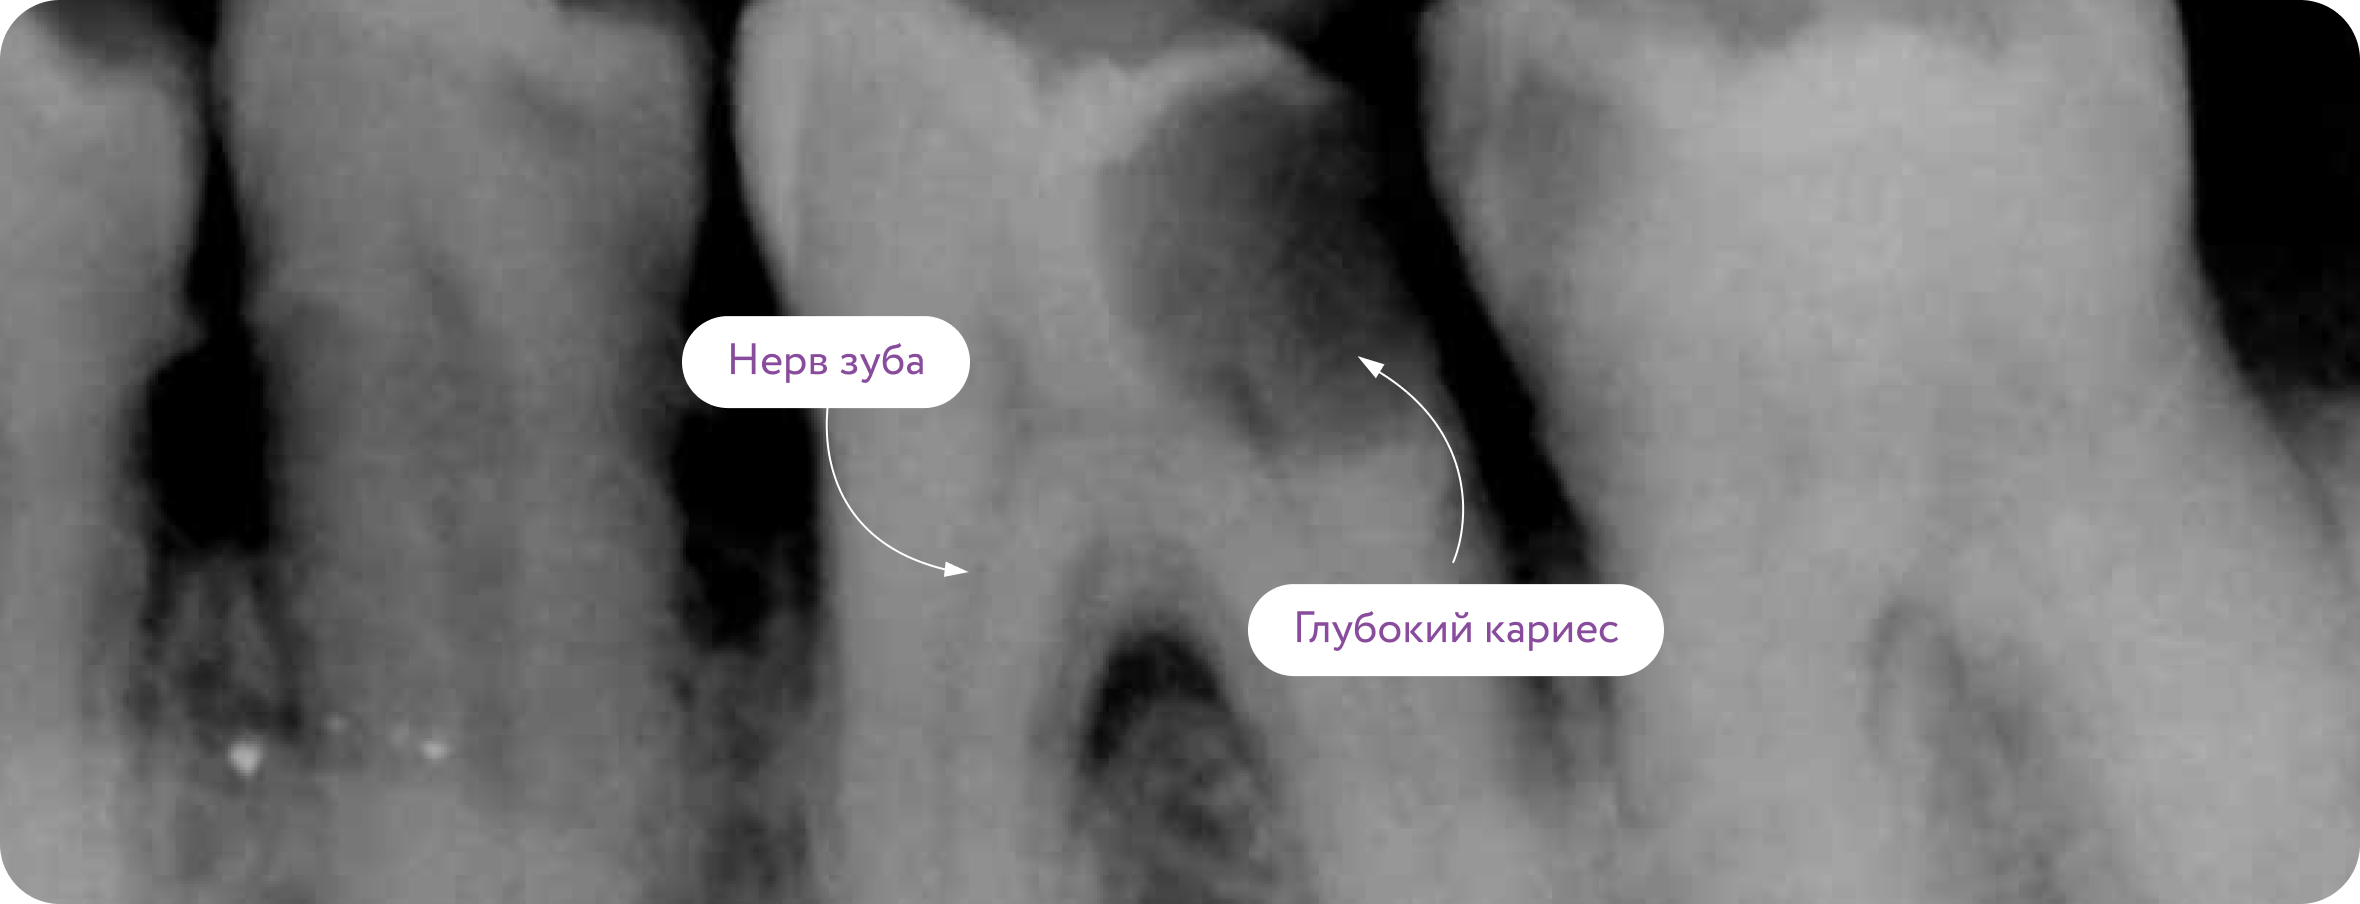

Лечение каналов (удаление нерва зуба) необходимо, когда кариес слишком глубоко проникает в зуб и поражает сосудисто-нервный пучок

Перелечивание каналов

Некачественно вылеченный зуб (затек слюны во время лечения, негерметичное пломбирование каналов, некачественные материалы) со временем может воспалиться и образовать кисту корня. В таких случаях требуется повторное лечение каналов

Воспаленный нерв медленно умирает и инфицируется, образуя кисту корня.

Стоматолог-терапевт промывает инфекцию, стерилизует каналы и заполняет их пломбировочным материалом